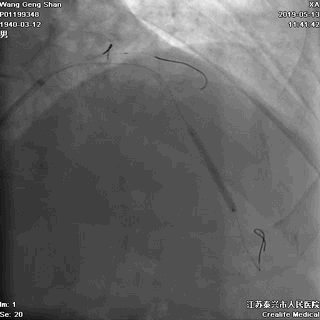

01 导丝进前三叉分支

02 处理LAD中段病变

上图,球囊预扩LAD中段病变

上图,LAD中段植入支架